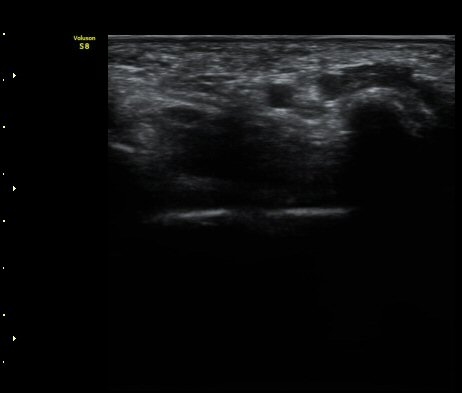

ÃÊÀ½ÆÄ °Ë»ç